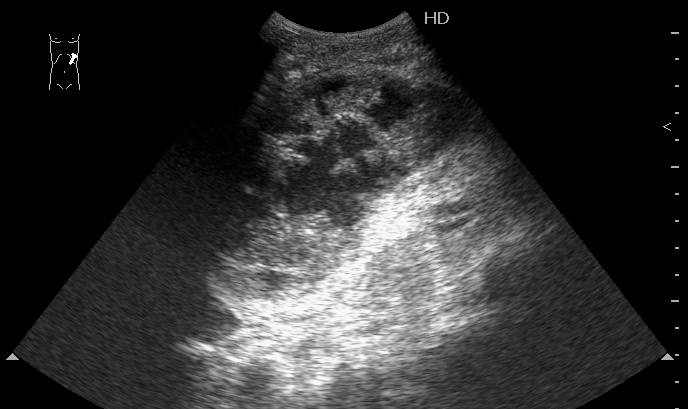

Мужчина 1952 г.р. поступил с болями в животе в БСМП. Длительное время страдал хроническим панкреатитом. Травму отрицает.

Мы вначале предпложили внутрикапсульный разрыв селезенки и ее разможжение, несмотря на отсутствие данных за травму (иногда наши пациенты имеют обыкновение её скрывать).

И ошиблись.

На секции - хронический панкреатит, псевдокиста селезенки. После вскрытия капсулы селезенки выделилась серая жидкость без примесей крови.

Механизм образования такой псевдокисты (?) мне лично непонятен, думаю обсудить это дело с университетскими анатомами.